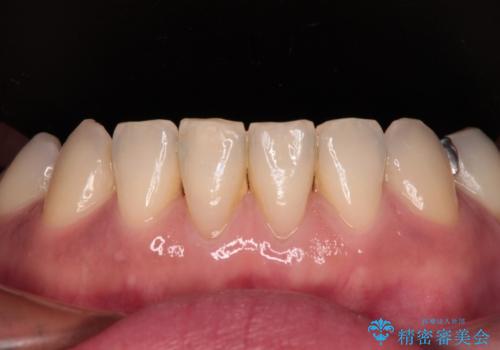

中途半端な矯正治療と前歯の欠損 再矯正とオールセラミッククラウンによる補綴治療

- 矯正治療を行ったものの、隙間やデコボコが多く、欠損している前歯も気になるとのことで来院された患者様です。

当初はセラミック治療だけを希望されていましたが、上下前歯のデコボコが顕著であったため、セラミッククラウンにて治療する前に再度矯正治療を行った方が仕上がりがきれいになると説明し、再矯正を行うこととしました。

矯正治療により前歯横幅のバランスを整えた後に、上顎前歯をオールセラミックブリッジにて補綴治療を行うこととしました。